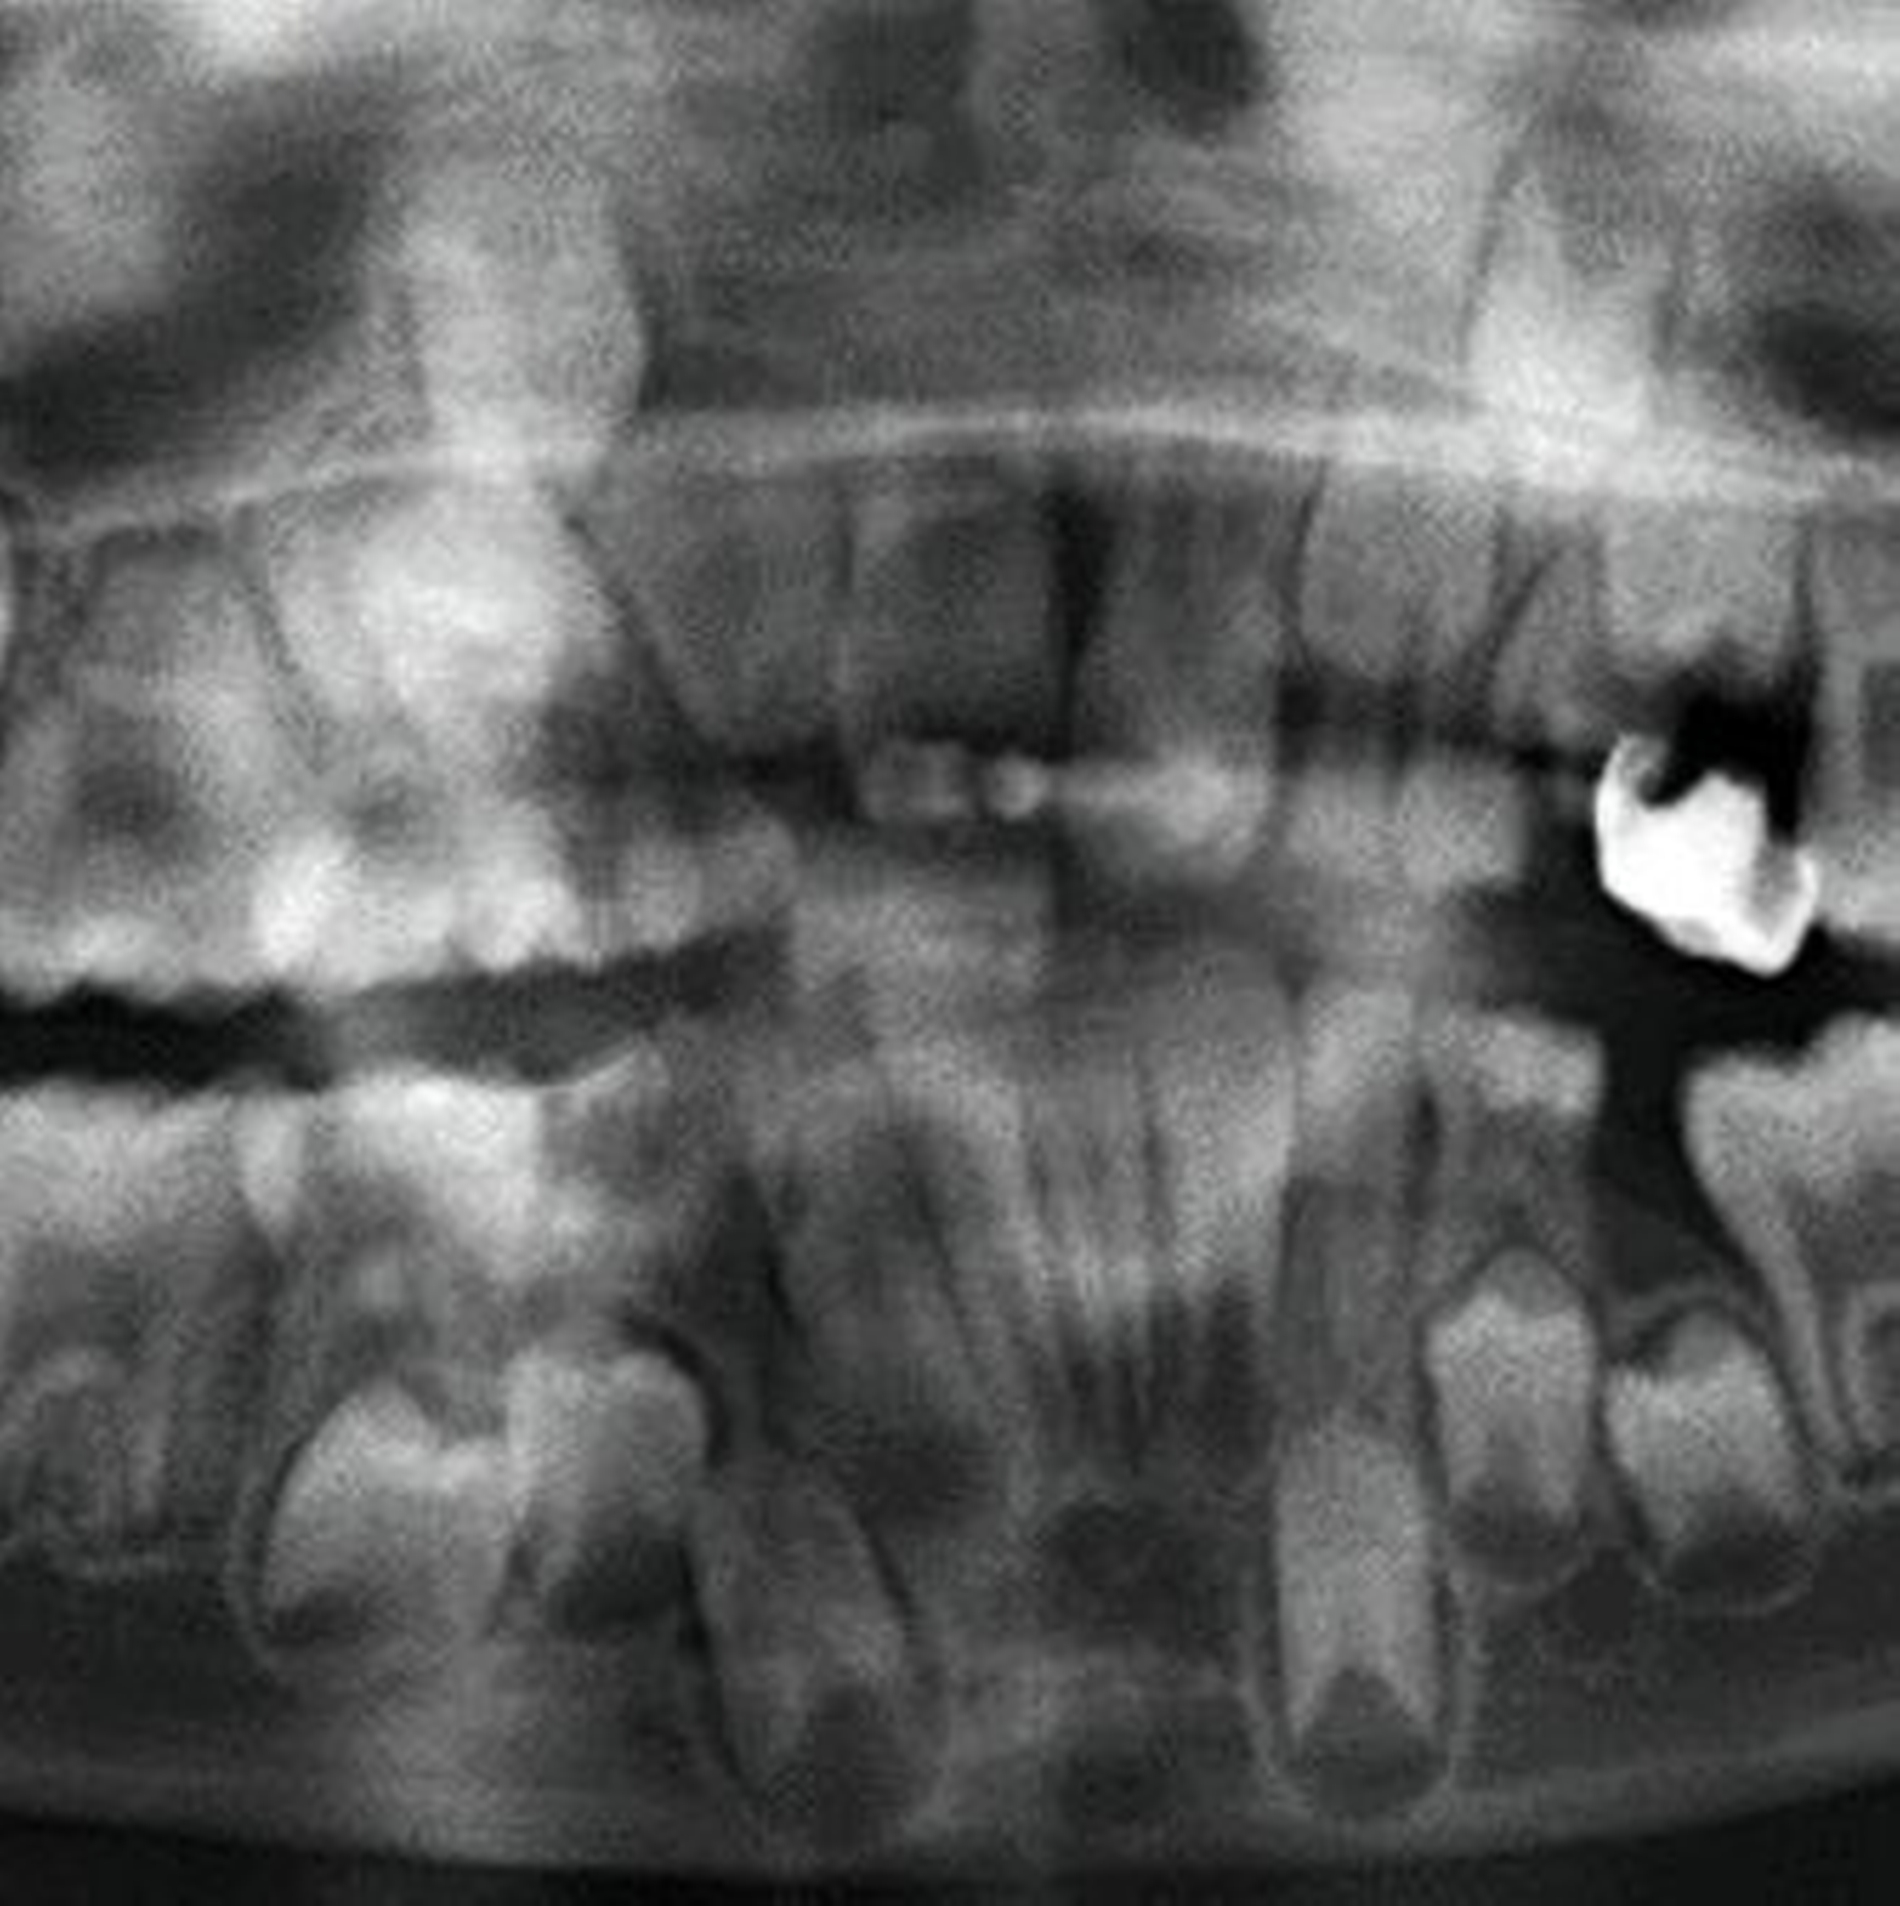

Eine Dekoronation ist eine chirurgische Intervention, die durchgeführt werden kann, wenn aufgrund ausgeprägter Schädigungen der desmodontalen Zellen und der Wurzeloberfläche eine Resorption auftritt. Im Rahmen der klinischen Untersuchung imponiert der betroffene Zahn aufgrund der Ankylose mit einem metallischen (hellen) Klopfschall. Röntgenologisch lassen sich Resorptionslakunen an der Wurzeloberfläche erkennen. Bei progressiver Resorption und Infraposition des betroffenen Zahnes in Relation zur Restdentition kann eine Dekoronation indiziert sein [Malmgren et al., 2015] (Abbildung 2).

Das Ziel der Dekoronation ist es, die klinische Krone unter Belassung der resorbierenden Wurzel zu entfernen, damit der Alveolarknochen aufgrund der Knochenneubildung bei Ersatzresorption erhalten und eine optimale Voraussetzung für spätere Interventionen gegeben werden kann [Malmgren et al., 2006]. Bei Patienten im Wachstum kann die Dekoronation eine sinnvolle Therapieoption darstellen, um den teils erheblichen Knochenverlust in Verbindung mit der chirurgischen Entfernung der ankylosierten Zahnwurzel zu vermeiden (Empfehlung 60).